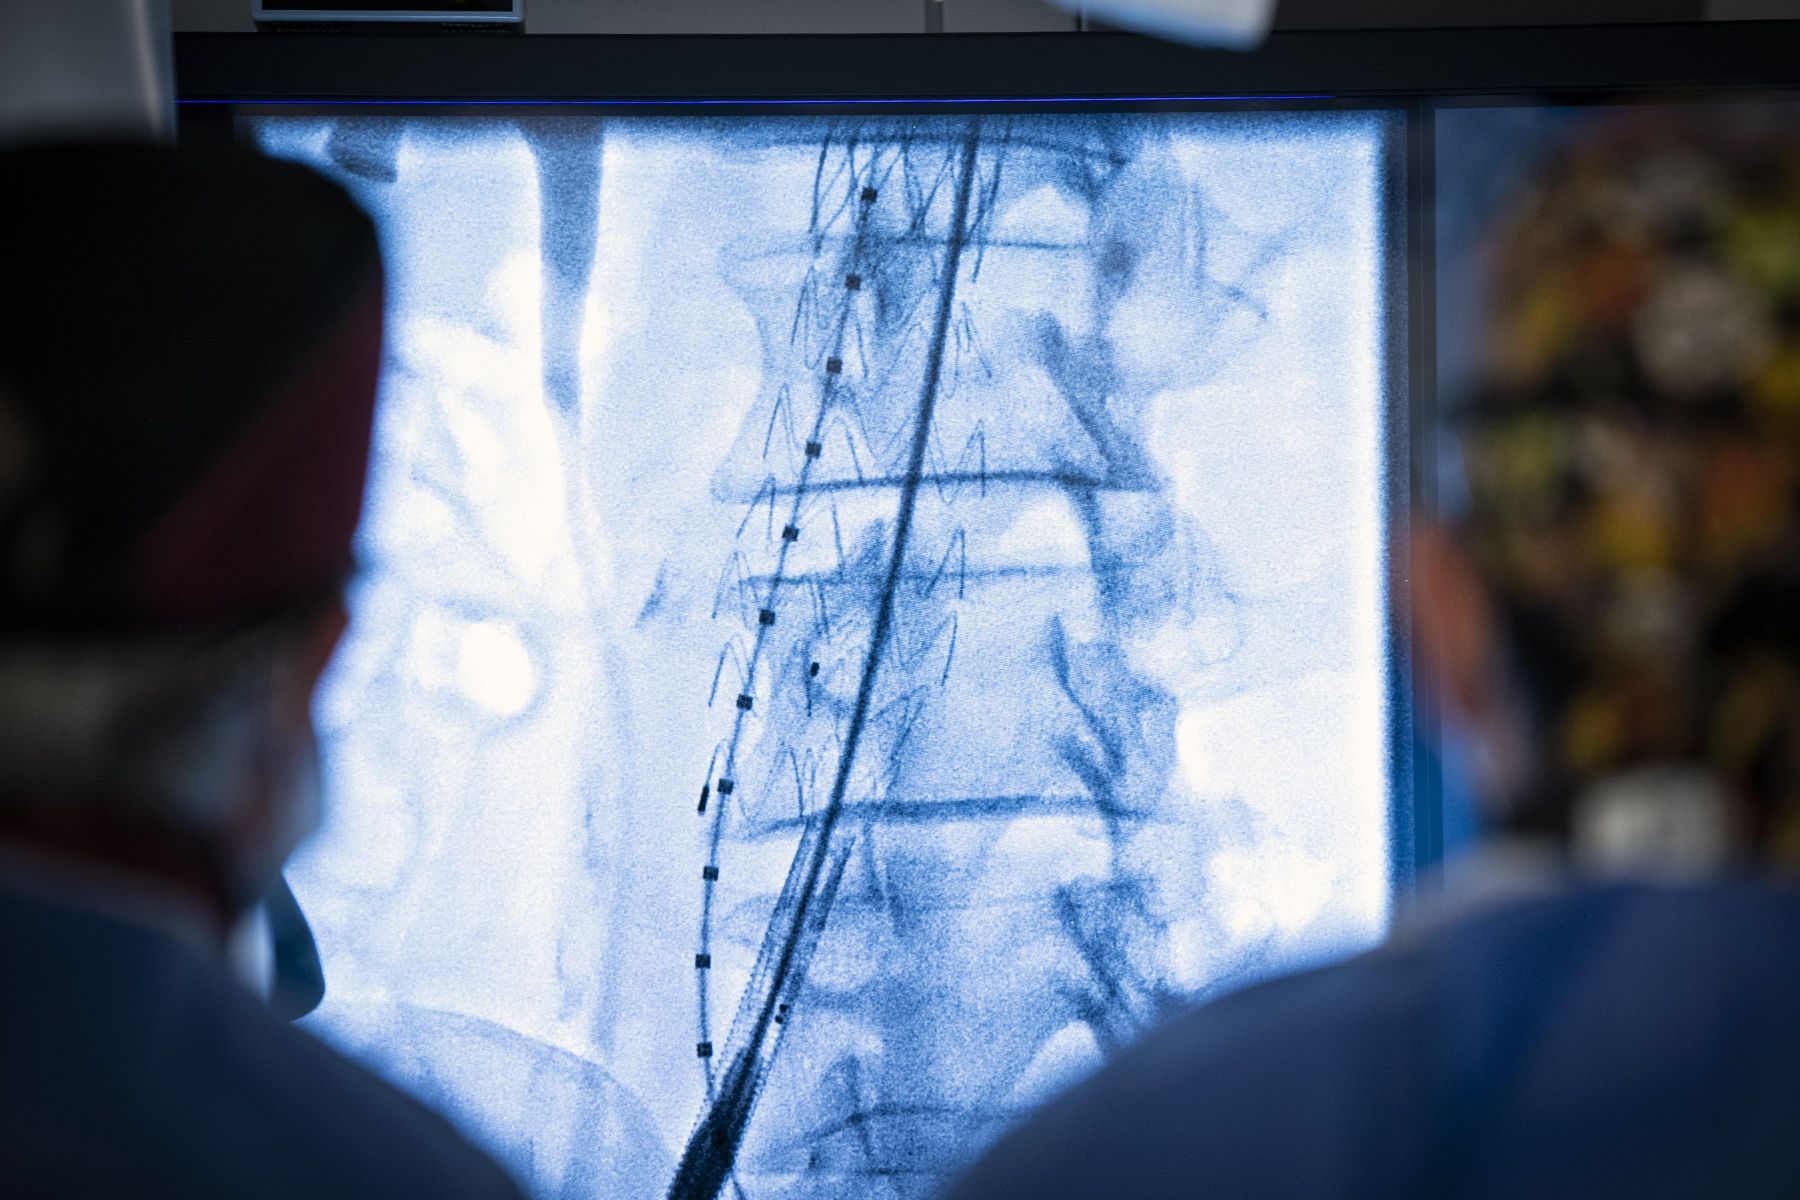

Instead of opening up the chest or abdomen in order to access the aorta, an EVAR is a minimally-invasive procedure in which medical teams insert a long tube carrying a stent graft (a metal mesh tube covered with fabric) into the main artery in the thigh and guide it to the area of the aorta with the aneurysm. Once placed, the stent graft works to restore normal blood flow and prevent the aneurysm from growing or bursting, which could cause life-threatening internal bleeding.

Multidisciplinary team (including nurses, vascular surgeon, interventional radiologist, interventional radiology technologist, and anesthesiologist) performing an endovascular repair of an aortic aneurysm in the new hybrid operating room.